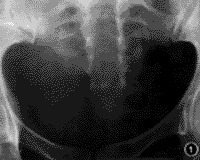

查体 发育营养中等,全身一般情况尚可。骶尾部稍偏左可见8cm×6cm的包块,表面皮肤颜色正常,质软,边界不清,移动差,触压时肛门、会阴部有疼痛、麻木感;肛周皮肤感觉迟钝;尾骨处有轻压痛,触摸时似有脱位;肛门括约肌收缩力弱,下肢感觉、运动正常;膝及跟腱反射正常,直腿抬高试验(-)。血、尿、便及肝功能常规实验室检查正常。腰骶部X线摄片显示骶椎隐性脊柱裂,骶尾交界处半脱位,远端向后脱位(图1,2)。MRI显示腰骶部脂肪瘤,脊髓低位,位于L4椎体下部,脂肪瘤经脊柱裂侵入椎管与终丝粘连形成栓系(图3,4)。

图1 隐性骶椎裂

图2 骶尾交界半脱位